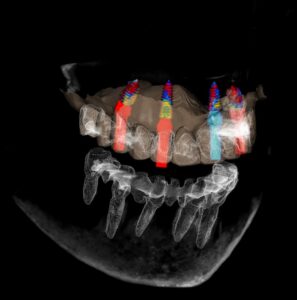

Durante la técnica All-on-4, se colocan cuatro implantes en el hueso maxilar, sobre los cuales se fija un denominado puente completo (una prótesis fija que reemplaza todos los dientes). Los dos implantes frontales se colocan verticalmente, mientras que los dos implantes posteriores se colocan en ángulo.

Posicionamiento de los implantes

La singularidad del All-on-4 reside en la colocación de los implantes:

- dos implantes en la parte frontal del hueso maxilar

- dos implantes en ángulo inclinado en la zona posterior

Dado que los implantes posteriores se colocan en ángulo inclinado, en muchos casos se puede evitar el injerto óseo, que es más frecuentemente necesario en las zonas posteriores.

- escáner CBCT (TC 3D)

En ocasiones utilizamos una guía quirúrgica, diseñada digitalmente con antelación, que permite colocar los implantes con precisión en la posición planificada previamente. Esto es especialmente importante en casos donde hay muy poco hueso disponible.